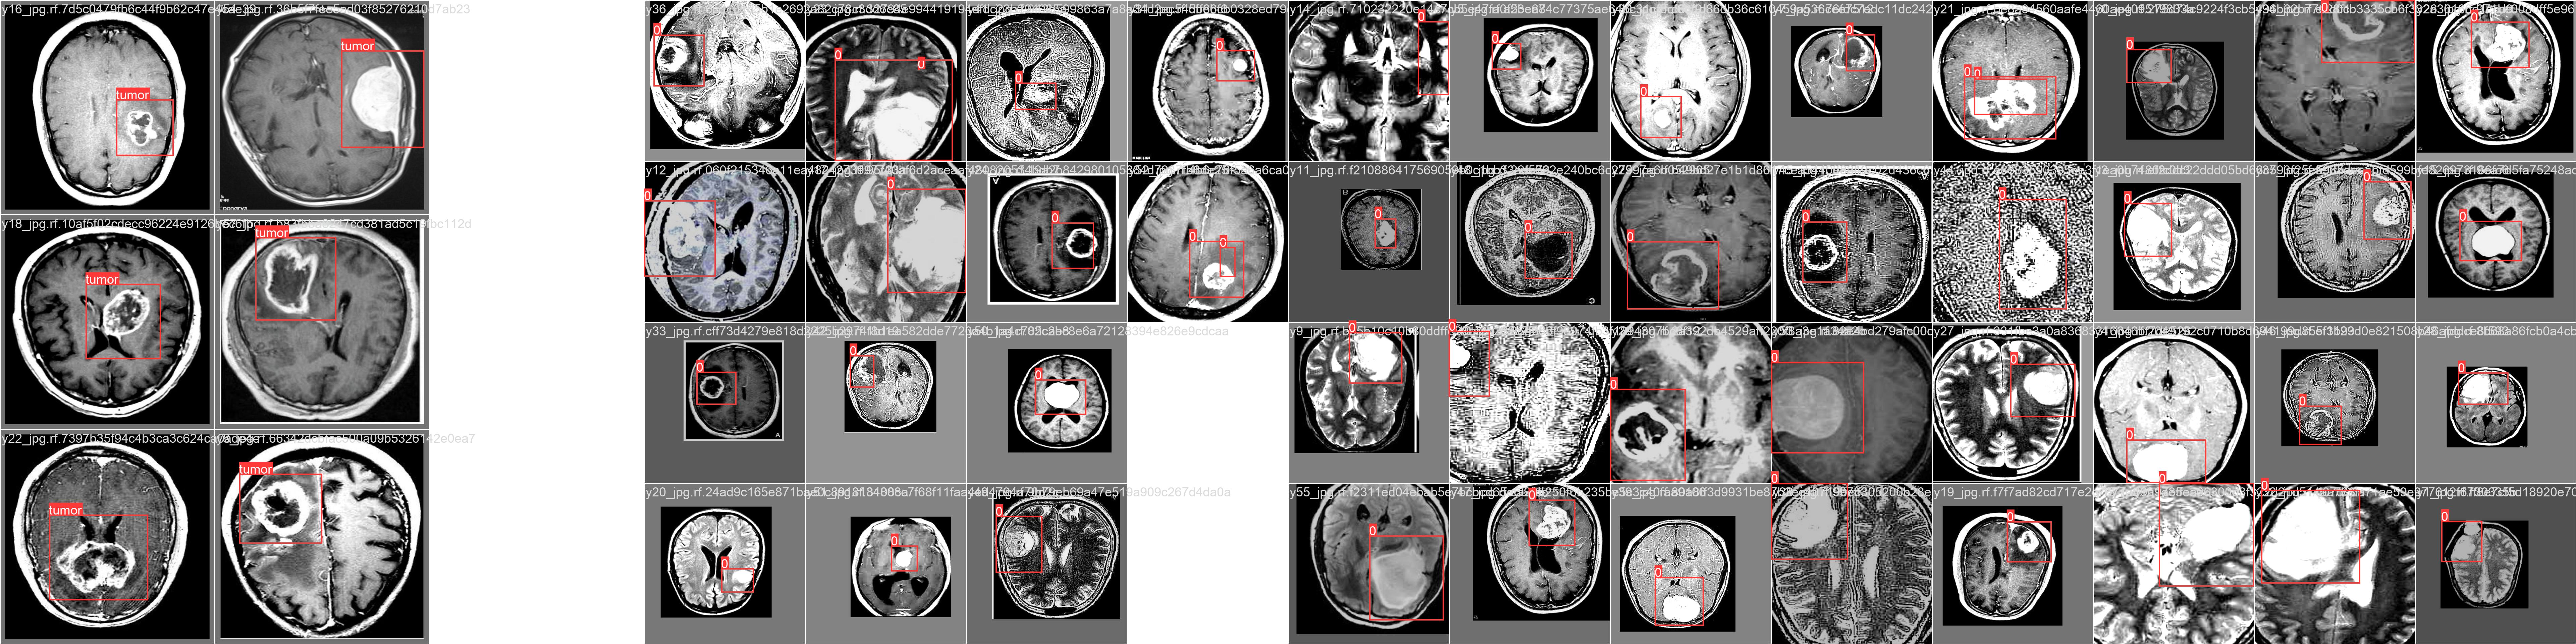

Ultralytics

Roboflow

OpenCV

My Portfolio

Some of the projects I've worked on.